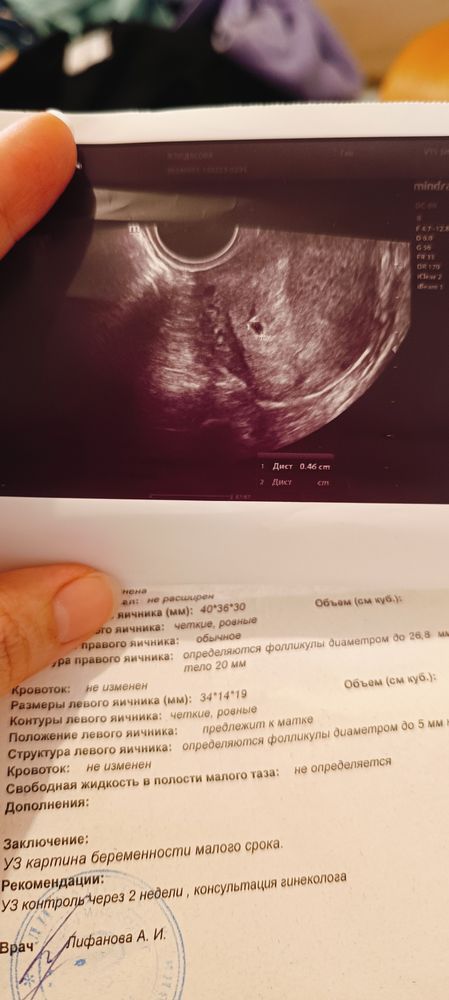

Дарья, спасибо ☺️, сегодня на узи подтвердили

Эва , вам тоже дали такое фото чудо Изображение

09.09.2024

Дарья, да , но пока очень крошечные, пя 0,18см